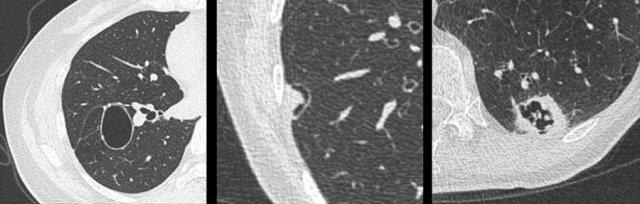

Ví dụ về ung thư phổi dạng nang với thành phần đặc hướng ngoại (bảng trái) và hướng nội (bảng phải).

- Thành phần đặc hướng ngoại hoặc hướng nội tiếp giáp với khoang khí dạng nang (hình).

- Dày thành không đều, một phần hoặc toàn chu vi.

- Hình ảnh phức tạp với các thành phần bán đặc và các khoang khí đa thùy.

Các hình ảnh minh họa thêm các ví dụ về ung thư phổi dạng nang với dày thành không đều mỏng (bảng trái) và dày (bảng giữa), cùng hình ảnh phức tạp hơn với kính mờ lan rộng và các khoang khí đa thùy (bảng phải).